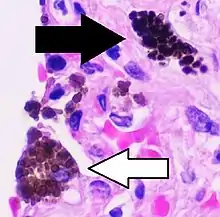

Comparison of pigmented pulmonary macrophages

| Disease | Macrophage name | Macrophage pigment appearance (HE stain) | Usual macrophage location | Associated medical history | Image | Image comment |

|---|---|---|---|---|---|---|

| Anthracosis | Black-brown granules | Interstitium (perivascular) |  |

Black arrow shows interstitial anthracotic pigment. Nearby macrophages (white arrow) can be presumed to contain anthracotic pigment. | ||